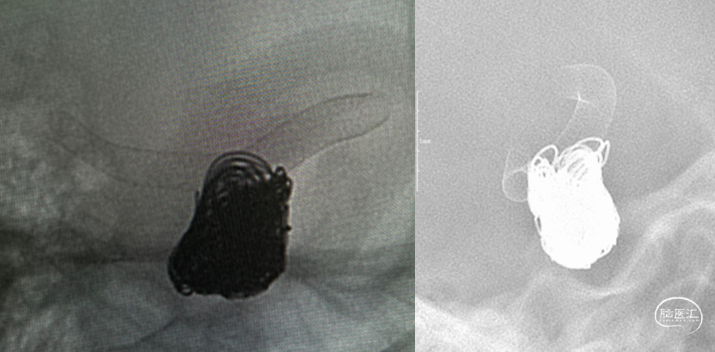

7、动脉瘤内继续填入弹簧圈将动脉瘤致密填塞,正位造影观察大脑中动脉血流通畅。

术后造影

1. 大型或巨大形动脉瘤,尤其梭形宽颈动脉瘤单纯弹簧圈栓塞后复发率较高;Pipeline™ 血流导向密网支架治疗可大大减少动脉瘤的复发;由于瘤颈较宽,可先进行瘤内部分栓塞,通过弹簧圈的填塞为血流导向密网支架提供一定的支撑,防止其在瘤腔内摆动,从而起到更好的血流导向作用,同时可降低密网支架释放过程中疝入动脉瘤的概率。

2. 支架释放时需注意头端的贴壁释放,尽量选择血管较为平缓位置缓慢释放,推拉过程中注意支架放置情况,在覆盖瘤颈口位置时注意支架与弹簧圈相对位置关系,稳定后再逐步释放完全。

3. 支架完全释放后,观察打开及贴壁良好,再逐步致密填塞动脉瘤,通过进一步填塞弹簧圈降低破裂风险。